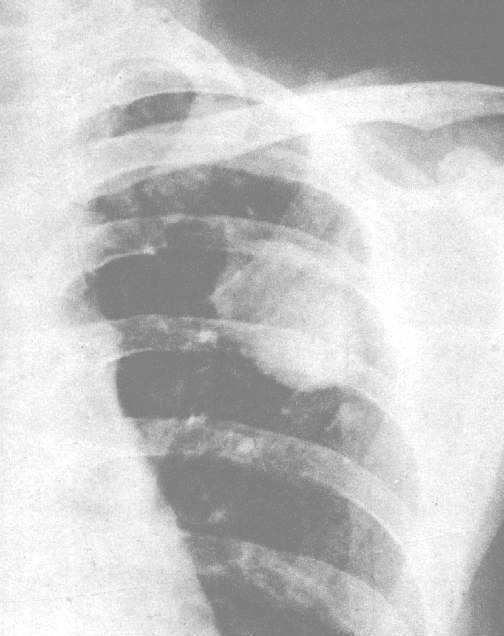

左上肺结核瘤。胸片示左锁骨下直径3.5x5.1cm团块影,为一层完整的包膜所环绕,上端包膜有粘连的现象,周围有卫星病灶。

1.结核瘤大多为孤立性球形病灶,多发者少见。多位于锁骨下区。形态常为圆形或椭圆形,有时可见分叶是由几个球形病灶融合在一起形成的。轮廓清晰锐利,有时环绕着一层约1-2mm宽度的线条包膜阴影。

4.结核瘤附近的肺野内可见有散在的结核病灶,即所谓的卫星病灶,对诊断有一定的帮助。